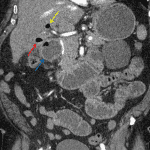

- Pneumobilia with intraluminal air in the gallbladder, which is nondistended

- Gallbladder wall thickening with pericholecystic fluid and loss of the normal fat plane between the gallbladder and duodenum

- Distended, fluid-filled loops of proximal and mid small bowel measuring up to 4.5 cm in diameter with transition point in the right lower quadrant where there are several peripherally calcified intraluminal structures

- Gallstone ileus

Findings concerning for acute cholecystitis complicated by gallstone ileus with several gallstones in the distal small bowel and mild upstream small bowel dilation. Recommend surgical evaluation.